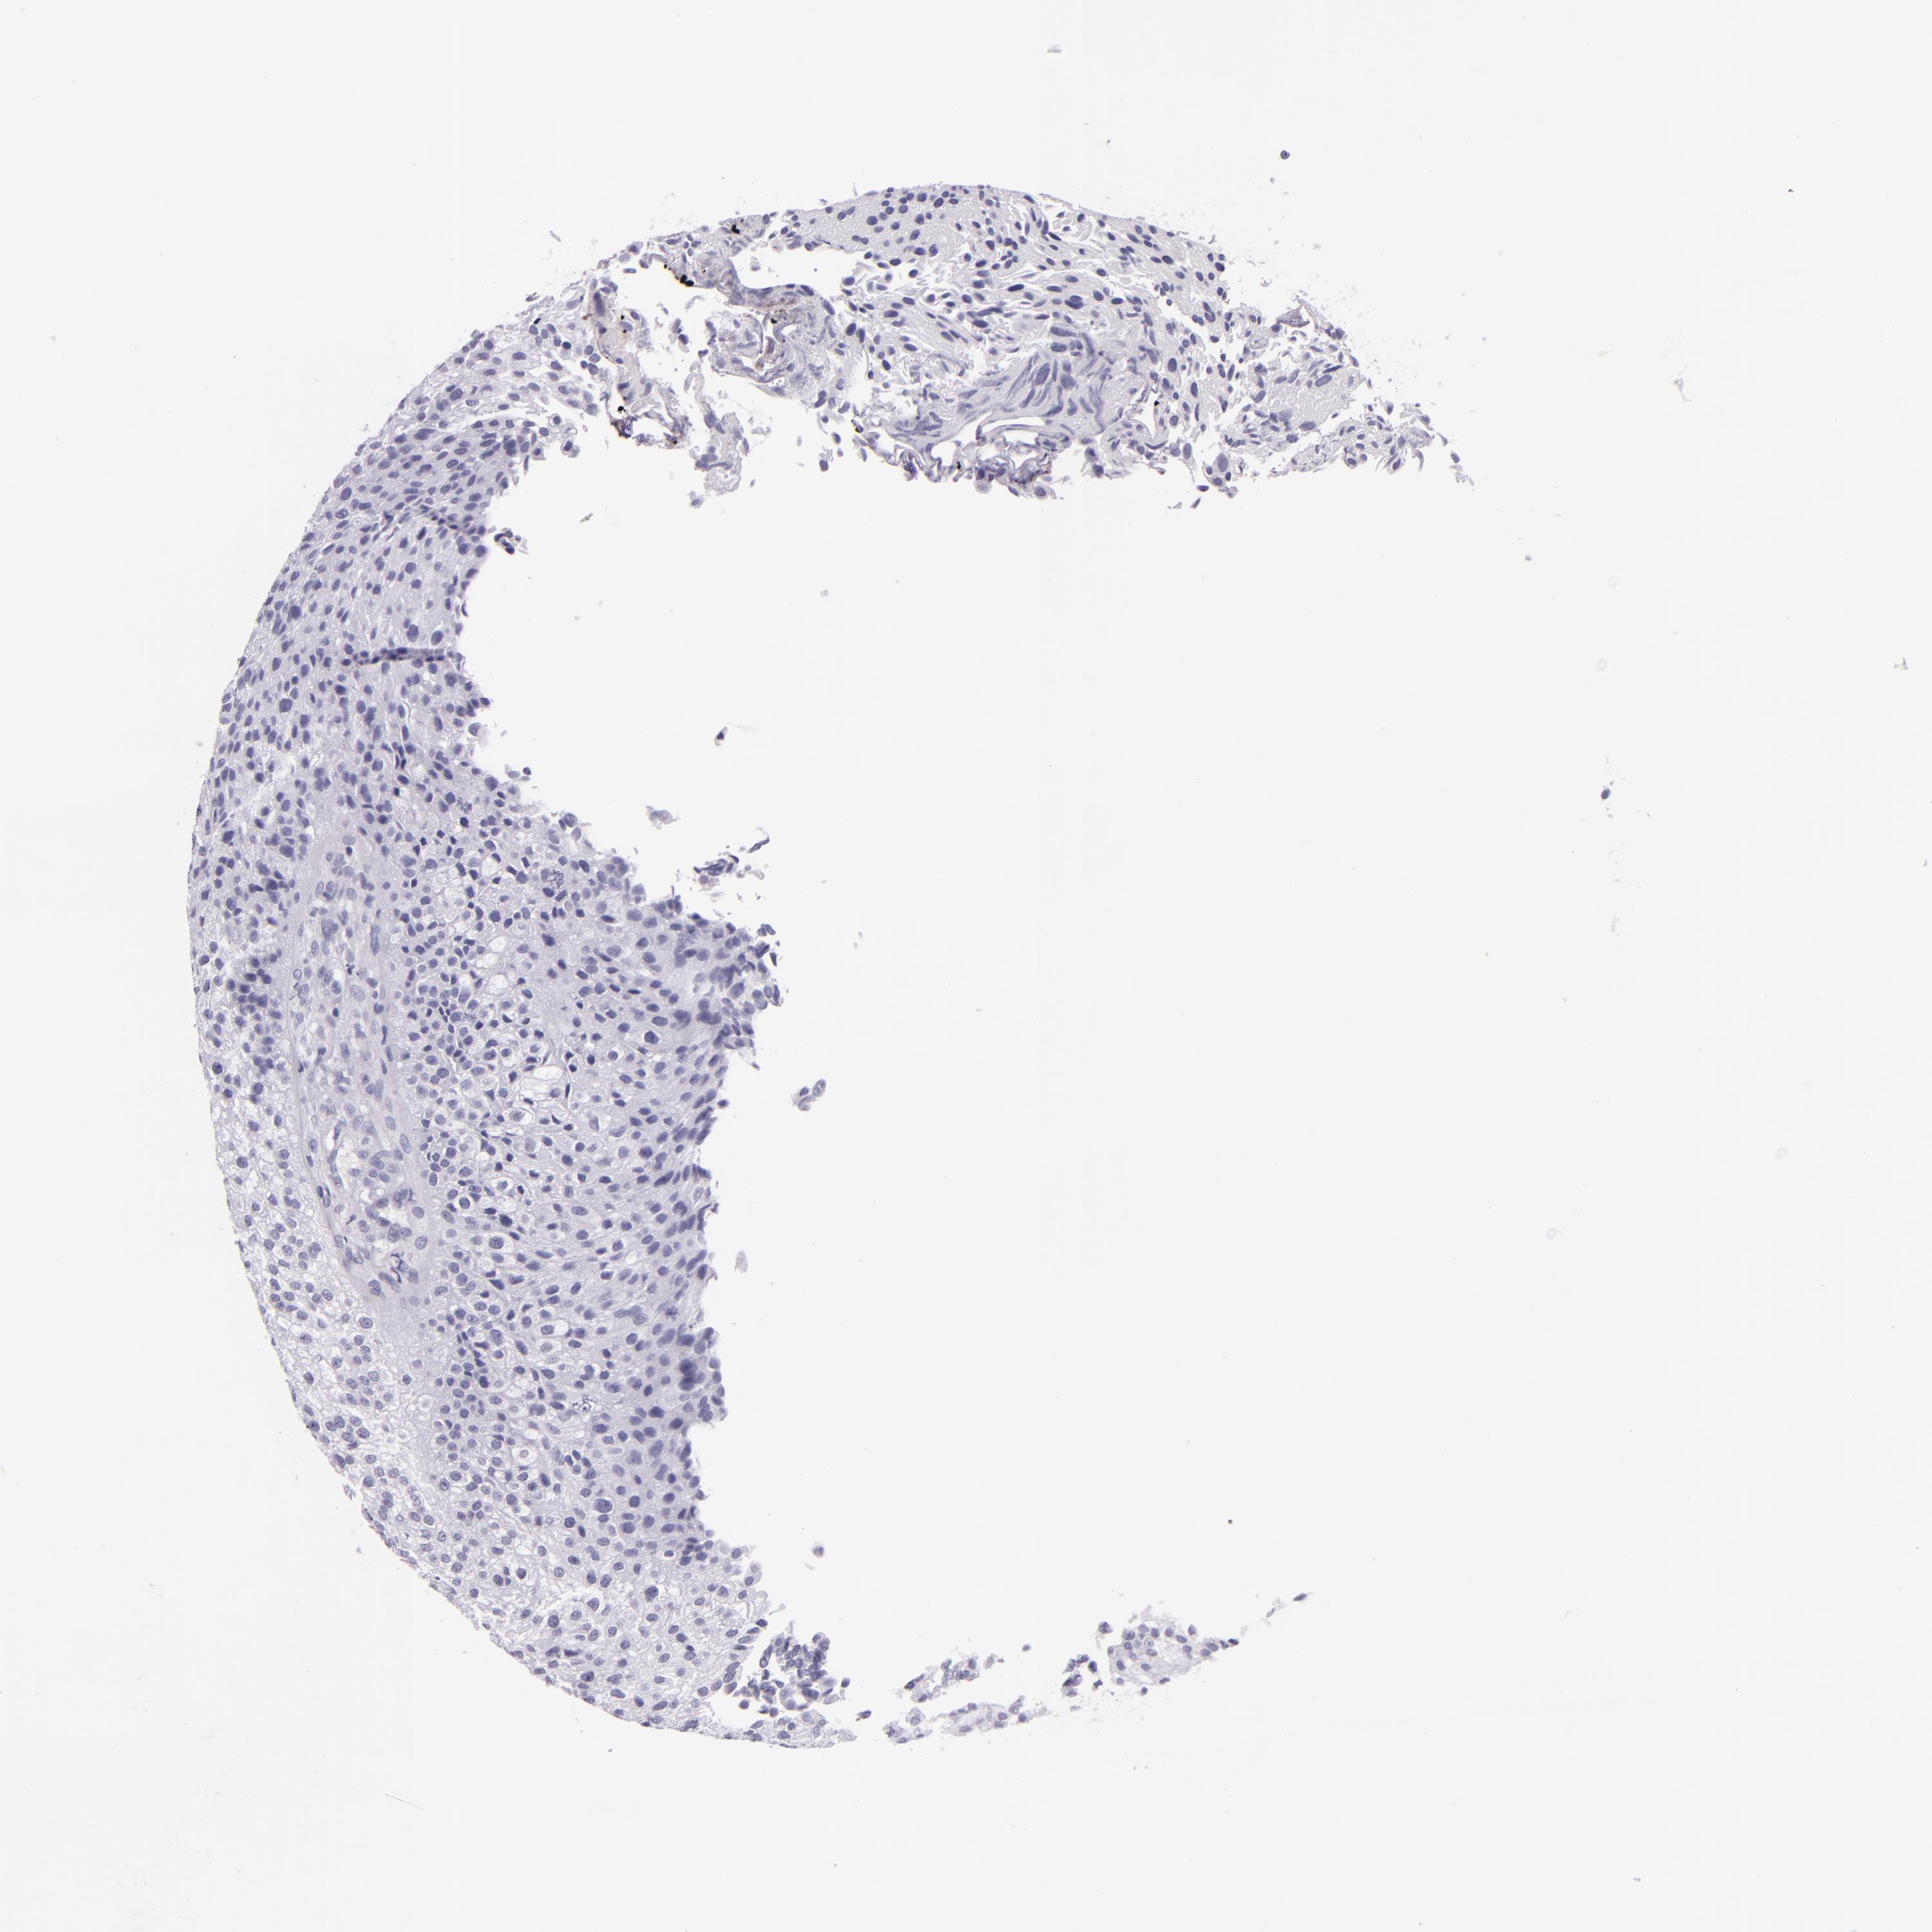

UROTHELIAL CANCER - Protein expressioni

A mouse-over function shows sample information and annotation data. Click on an image to view it in a full screen mode. Samples can be filtered based on level of antibody staining by selecting one or several of the following categories: high, medium, low and not detected. The assay and annotation is described here.

Antibody stainingi

Antibody staining in the annotated cell types in the current human tissue is reported as not detected, low, medium, or high, based on conventional immunohistochemistry profiling in selected tissues. This score is based on the combination of the staining intensity and fraction of stained cells.

Each image is clickable and will lead to virtual microscopy that enables deeper exploration of all samples and also displays staining intensity scores, fraction scores and subcellular localization as well as patient and tissue information for each sample.

Antibody CAB002161

Antibody CAB013056

Urothelial carcinoma, High grade

Urothelial carcinoma, Low grade

Adenocarcinoma, NOS